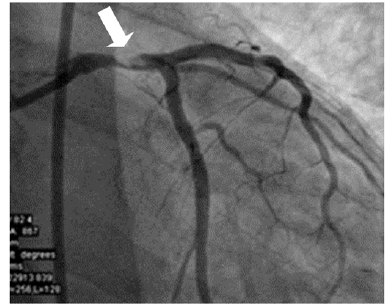

Um paciente de 55 anos de idade, diabético, vem apresentando dor torácica de início recente. São realizados ecocardiograma e cateterismo cardíaco. No ecocardiograma, percebe-se função ventricular conforme a imagem diminuída (40%), com hipocinesia de parede.